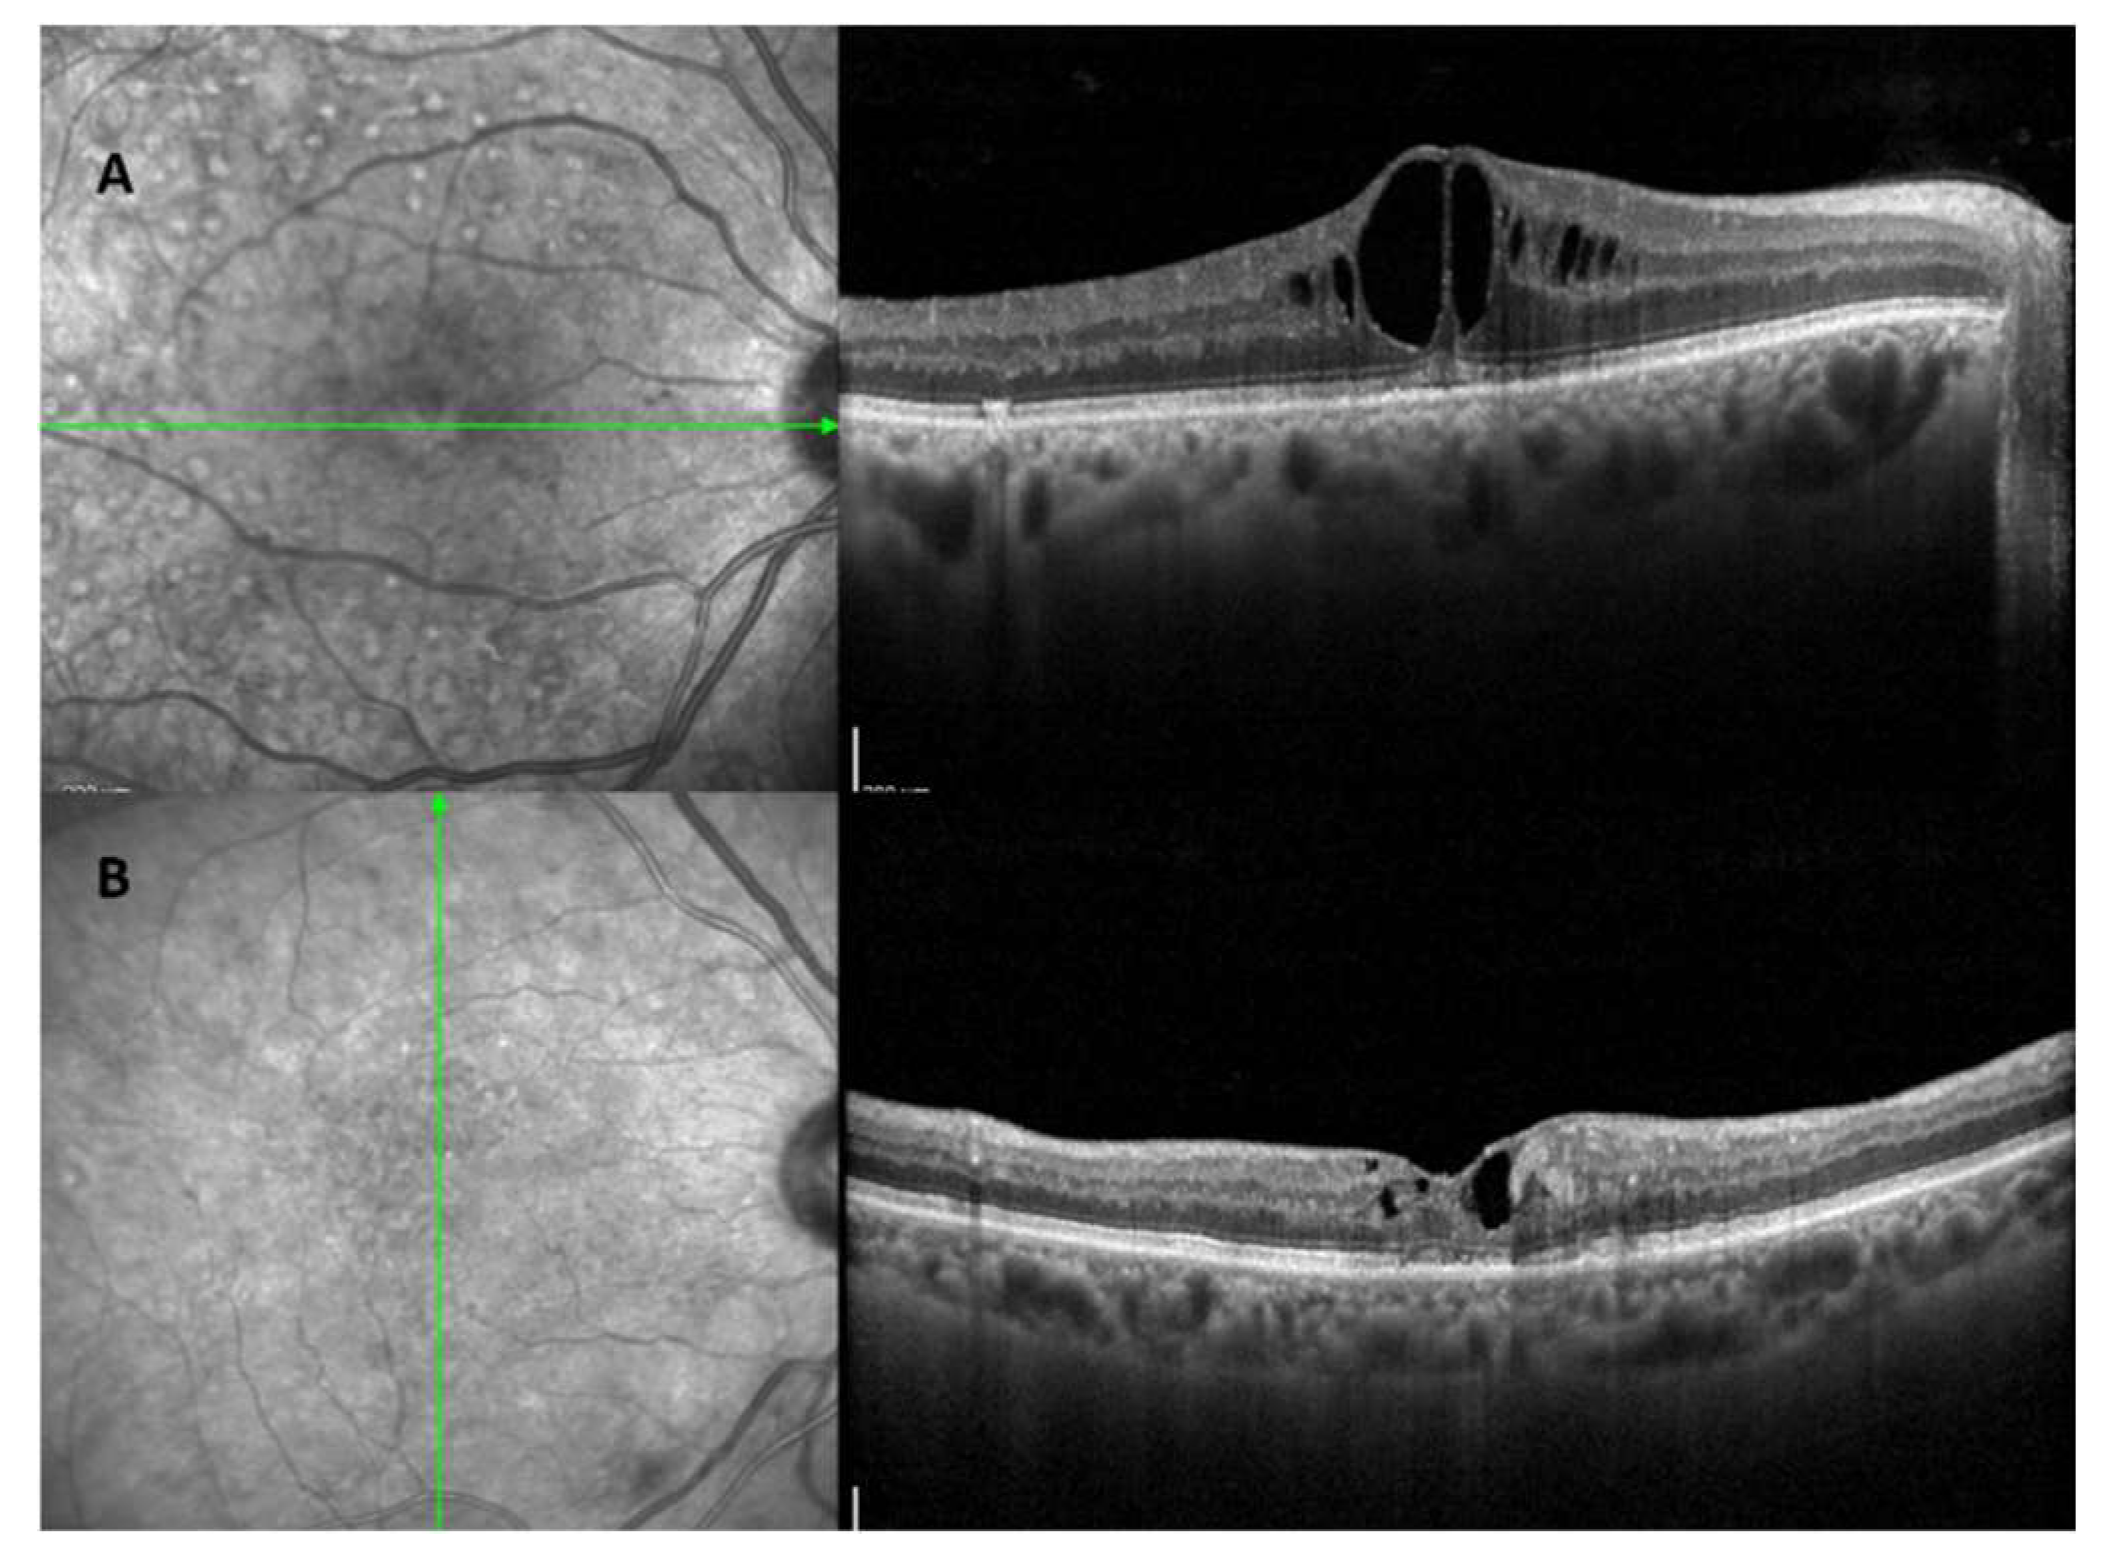

3. Advancements in Diagnostic Techniques of Diabetic Retinopathy

Recent advances in retinal imaging have greatly improved the early detection and management of diabetic retinopathy (DR). Color fundus photography, which is useful for screening and monitoring DR, shows key disease indicators such as microaneurysms, retinal hemorrhages, and changes in intraretinal capillaries and veins [42]. Fluorescein angiography (FA), although invasive and time-consuming, is effective in detecting capillary occlusion, new vessel growth, macular ischemia, and distinguishing between localized and widespread retinal edema [43]. This method distinguishes between focal macular edema, characterized by localized retinal thickening, and diffuse macular edema, characterized by generalized leakage and accumulation of dye in the retina. However, due to the invasive nature of FA, many ophthalmologists now rely solely on optical coherence tomography (OCT) for the management of DME [44]. OCT, which provides faster and more accurate assessments, measures central retinal thickness (CRT) to evaluate DME severity and treatment response. It also identifies different patterns of DME, such as diffuse retinal thickening, cystoid macular edema, and serous retinal detachment [45]. Recently, OCT has distinguished two types of DME based on unique biomarkers and treatment response: the vascular DME phenotype (Figure 3A), which is mainly due to inner blood-retinal barrier dysfunction and responds to anti-VEGF therapy, and the inflammatory DME phenotype (Figure 3B), which typically responds better to steroids [44,46,47]. The latter is linked to elevated cytokine levels in eye fluids, contributing to retinal changes [44]. Features like multiple hyperreflective foci and serous retinal detachment, observed in 36.5% of DME eyes, are considered inflammation indicators, associated with increased hyperreflective foci and interleukin-6 levels [44,48].

Figure 3. A: OCT shows an inflammatory diabetic macular edema (DME) phenotype characterized by hyperreflective spots and intraretinal cysts with increases in central subfoveal thickness B: OCT reveals a vascular DME phenotype characterized by small cystoid space and hard exudates.